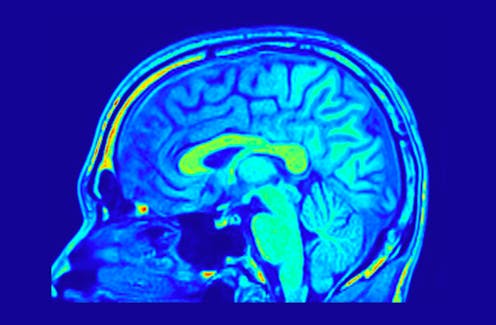

For magnitude, the question is: is the extent of any differences clearly and accurately described? Take this 2015 study on sex differences in the human brain. It reported on 34,716 different patterns of functional brain connectivity, and found statistical differences between females and males in 178 of them.

Yet given that less than 0.5% of all possible differences they were measuring actually turned out to be statistically significant, they wouldn’t really be justified in reporting sex differences as prominent. In this study, they weren’t.